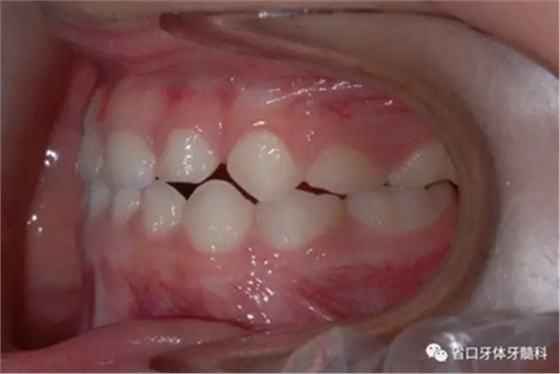

圖4 正面牙相(2015年1月)